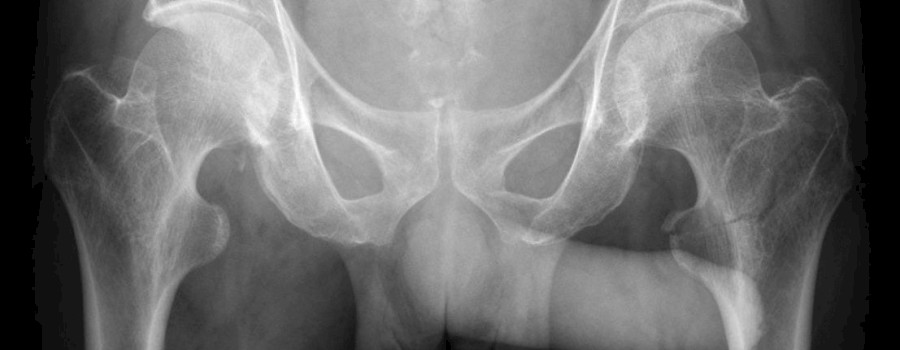

Röntgenzeichen sind in der klinischen Befundung eine wertvolle Hilfe. Die meisten Röntgenzeichen sind so typisch, dass sie gemeinsam mit den klinischen Befunden eine Diagnose beweisen.

Röntgenzeichen, sind typische Abweichungen vom Normalbefund eines Röntgenbildes (bzw. in einem anderen bildgebenden Verfahren), die auf eine bestimmte Erkrankung hinweisen.